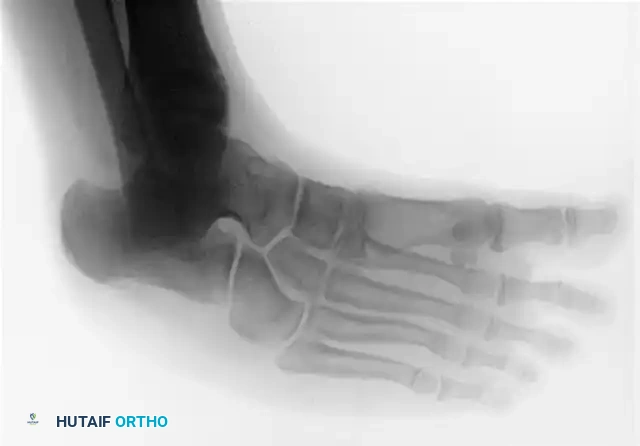

FIGURE 82-76 C: Congenital talonavicular tarsal coalition (Oblique view).